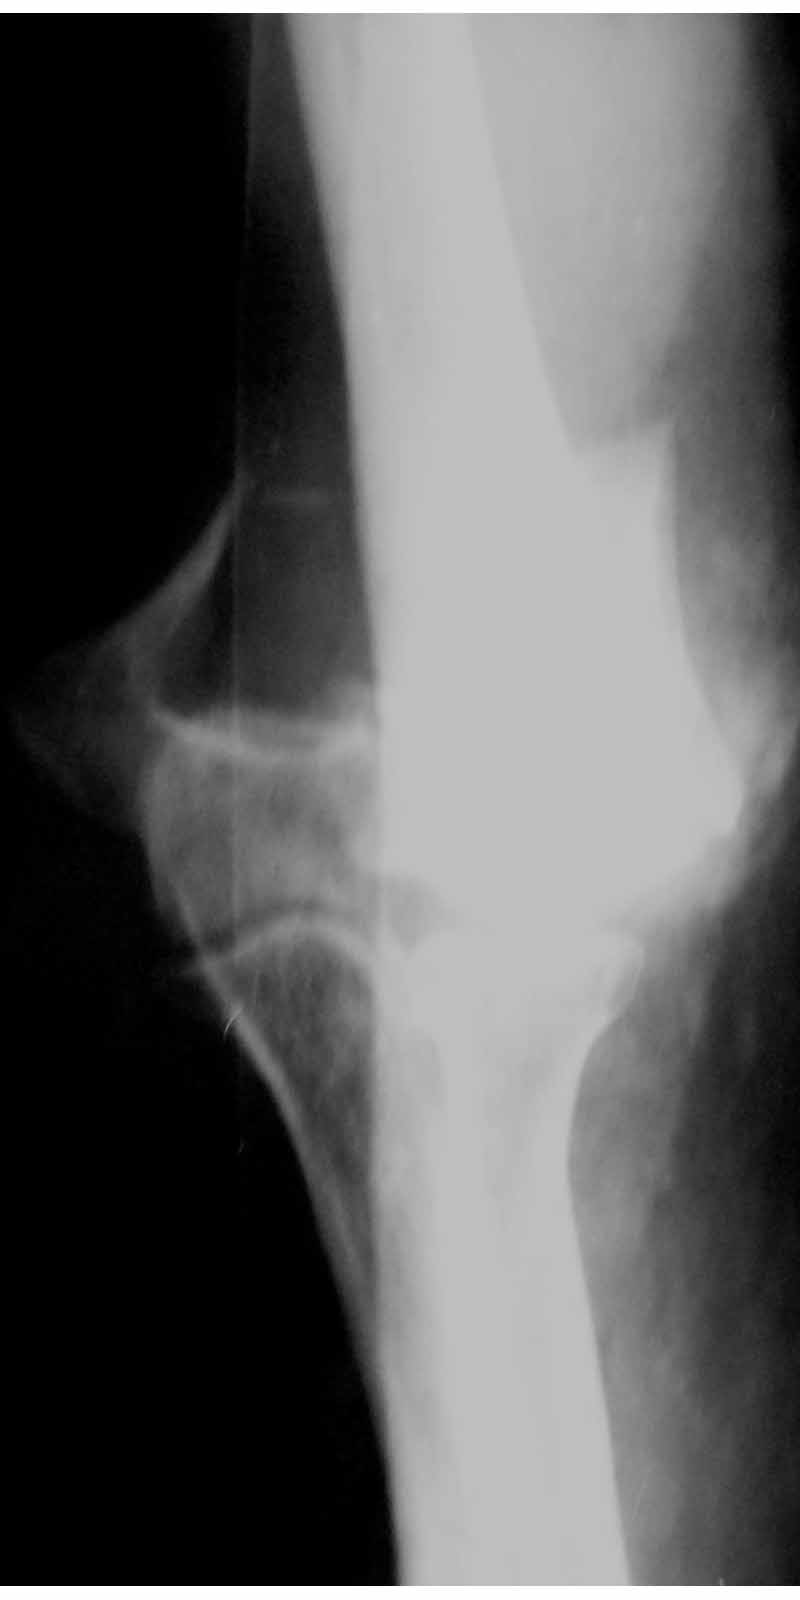

Женщина 42 лет, операция через неделю после перелома.

Д-з - открытый перелом мыщелков со смещзением и локтевой кости

без смещения - падение с лошади.

До операции снимки не очень, тем более в гипсе.

Остеосинтез закрытый (если так можно выразиться), т.е. без

разрезов. Длительность операции - около 1,5 часа со студентом.

6 щелчков ЭОПом.